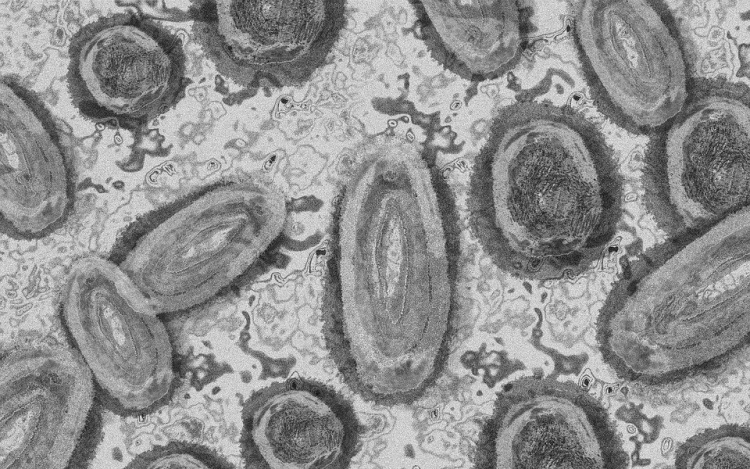

Belgiumban egy 3 év alatti gyermek fertőződött meg majomhimlővel - számolt be róla szerdán a Sudinfo hírportál.

Steven Van Gucht, a belga közegészségügyi intézet (Sciensano) fertőző betegségekkel foglalkozó osztályának vezetője azt nyilatkozta, hogy nagyon kivételes esetről van szó, a gyermeket valószínűleg saját szülei fertőzhették meg. Véleménye szerint nagyon ritka, hogy a fertőzés szülőről gyerekre terjed, de előfordulhat. Mint mondta, a gyermekek tünetei általában enyhék.

"A betegségben szenvedőknek nagyon kell vigyázniuk, hogy ne fertőzzék meg gyermekeiket. Akár egy törölközővel is át lehet adni a fertőzést" - magyarázta Marc Van Ranst virológus professzor a helyi sajtónak. Európában eddig 29 fertőzést igazoltak gyermekeknél.

Belgiumban a járvány kezdete óta 671 majomhimlős esetet regisztráltak a Sciensano kedden közzétett adatai szerint. 360 fertőzöttet Flandriában, 236-ot Brüsszelben és 75-öt Vallóniában jegyeztek fel, szinte minden érintett 16 és 71 év közötti férfi.

Harmincegy ember került eddig kórházba, egyikük sem szorult intenzív ellátásra. Halálos kimenetelű esetekről nem érkezett jelentés. A Sciensano tájékoztatása szerint a Belgiumban jelenleg rendelkezésre álló 3220 adag majomhimlő elleni oltóanyagból 1153 adagot használtak fel.